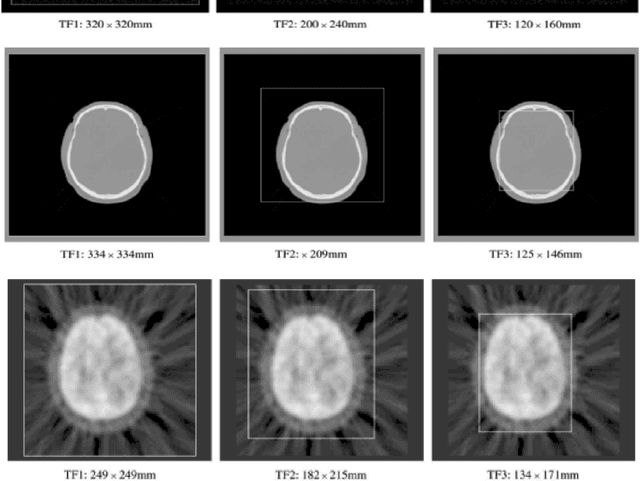

Abstract:Medical image registration plays an important role in determining topographic and morphological changes for functional diagnostic and therapeutic purposes. Manual alignment and semi-automated software still have been used; however they are subjective and make specialists spend precious time. Fully automated methods are faster and user-independent, but the critical point is registration reliability. Similarity measurement using Mutual Information (MI) with Shannon entropy (MIS) is the most common automated method that is being currently applied in medical images, although more reliable algorithms have been proposed over the last decade, suggesting improvements and different entropies; such as Studholme et al, (1999), who demonstrated that the normalization of Mutual Information (NMI) provides an invariant entropy measure for 3D medical image registration. In this paper, we described a set of experiments to evaluate the applicability of Tsallis entropy in the Mutual Information (MIT) and in the Normalized Mutual Information (NMIT) as cost functions for Magnetic Resonance Imaging (MRI), Positron Emission Tomography (PET) and Computed Tomography (CT) exams registration. The effect of changing overlap in a simple image model and clinical experiments on current entropies (Entropy Correlation Coefficient - ECC, MIS and NMI) and the proposed ones (MIT and NMT) showed NMI and NMIT with Tsallis parameter close to 1 as the best options (confidence and accuracy) for CT to MRI and PET to MRI automatic neuroimaging registration.